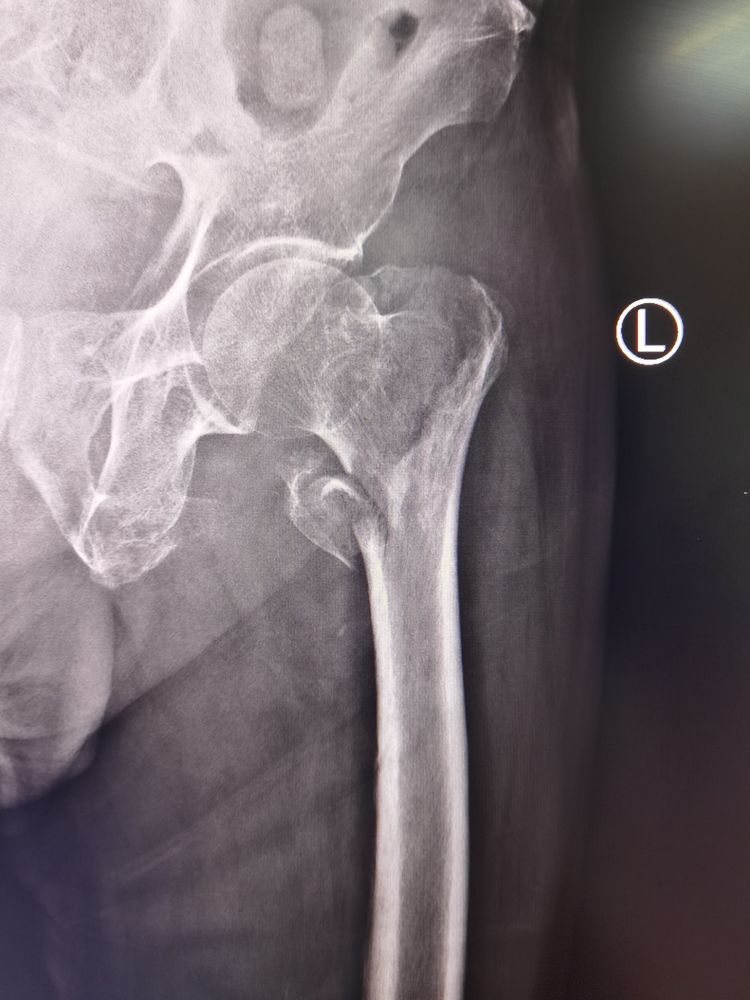

患者81岁高龄男性,因反复胸闷、气短3年,于省级三甲医院诊断为“难治性心力衰竭”,并多次住院治疗,长期口服抗心衰药物控制病情;2020.8.2患者不慎摔伤,就近三甲医院住院,诊断为“左侧股骨粗隆间骨折”,考虑患者病情危重,期间多次会诊后不予安排手术治疗;故于2020.8.11转至我院心血管二病区,由卢玉俊副主任医师团队收治,诊断为:慢性心力衰竭急性加重、心功能Ⅳ级,左侧股骨粗隆间骨折,双侧胸腔积液并双肺下叶膨胀不全,多处Ⅲ期压疮。经过卢玉俊副主任医师团队的精心治疗后患者内科症状得到一定改善;为进一步控制患者病情,由麻醉手术科冯秀玲主任牵头,关节外科曾昭洋主任及ICU王煜主任共同会诊后,进行充分论证,精心准备,于2020.8.22上午9时患者接入手术室,由于患者有严重的腰椎侧弯畸形,增加麻醉难度,由冯秀玲主任亲自为患者实施椎管内麻醉,待麻醉成功后,患者出现房颤,心率很快由70上升至120次左右,在冯秀玲主任医师麻醉团队有条不紊地对症治疗下,患者心率得到控制;接下来由曾昭洋主任医师团队闭合复位左侧股骨粗隆间骨折,C臂透视下实施PFNA内固定术,手术历时30分钟,骨折断端复位满意,内固定牢靠,术后转至我院重症医学科(ICU),由王昱主任医师ICU团队接手继续患者术后治疗,目前患者病情在ICU医师团队的密切治疗下,术后恢复良好。

术中透视